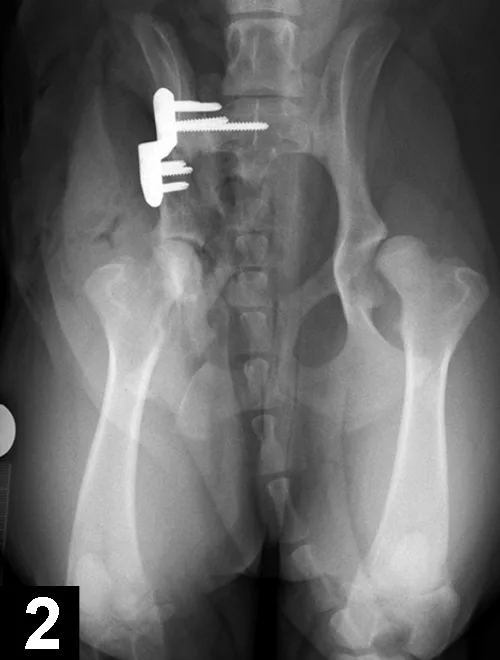

Elbow dysplasia is an umbrella term for several conditions (eg, ununited anconeal process [UAP], medial coronoid disease [MCD], osteochondrosis [OC]/OCD, incongruency) resulting in OA. Most patients are affected by only 1 or 2 of these conditions at the same time (eg, fragmented medial coronoid process, humeral OCD). The causes are multifactorial; genetic and environmental factors are involved. Dogs present with unilateral or bilateral lameness or stiffness of the forelimbs with effusion, pain, and decreased range of motion of the elbow. In dogs older than 5 months of age, radiographs of the joint may show a radiolucent line in the anconeal process (ie, UAP; Figure 3), an articular defect in the medial aspect of the humeral condyle (ie, OC, OCD; Figure 4), sclerosis and blunting of the medial coronoid process (ie, MCD), degenerative changes, or joint incongruency.

MCD (with or without fragment) is the most common among these conditions. Advanced imaging techniques (eg, CT) help in visualization of the coronoid process, which may appear fragmented or sclerotic (Figure 5), be associated with osteophytosis, or have radial incisure irregularities.